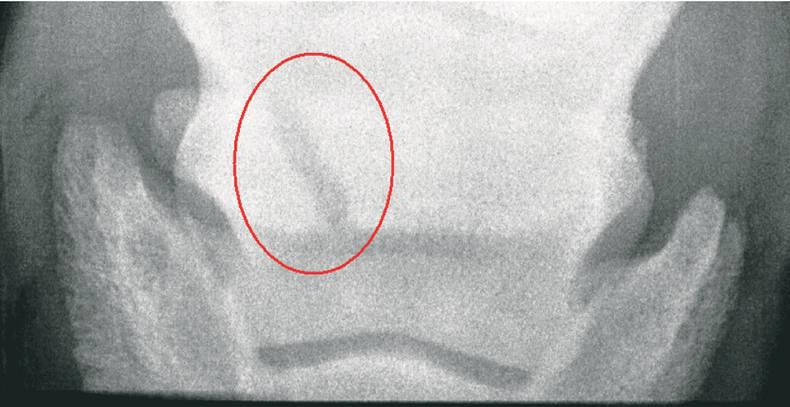

Within the hoof there are two main bones, the pedal bone and the smaller navicular bone. The pedal bone is the large bone that attaches to the hoof wall and provides strength and stability. The navicular bone meanwhile is a small bone, which lies behind the pedal bone.